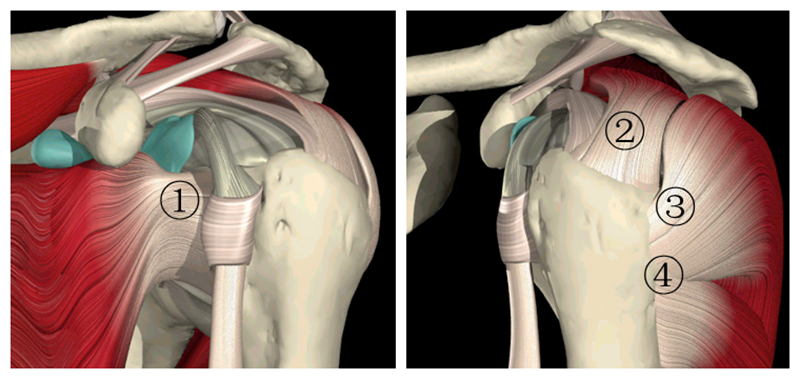

肩袖是由冈上肌、冈下肌、肩胛下肌及小圆肌的腱性部分组成的鞘状结构。它包绕盂肱关节、肱骨头、关节囊,形成近似袖套样肌样结构,具有保持肱盂关节稳定,维持上臂各种姿势和完成各种运动的功能。

图2 肩袖解剖1.肩胛下肌2.冈上肌3.冈下肌4.小圆肌